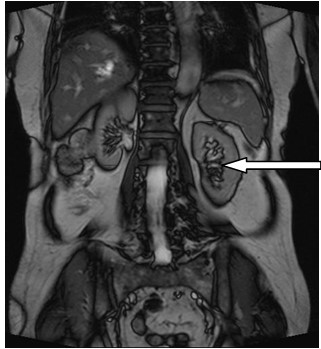

Świadczenie usług medycznych …

Jakie struktury anatomiczne uwidoczniono na obrazie USG?

Ilustracja do pytania 33

A. Pęcherz moczowy z kamieniami.

B. Ciężarna macica z czterema płodami.

C. Nerka lewa ze złogami.

D. Pęcherzyk żółciowy z kamieniami.